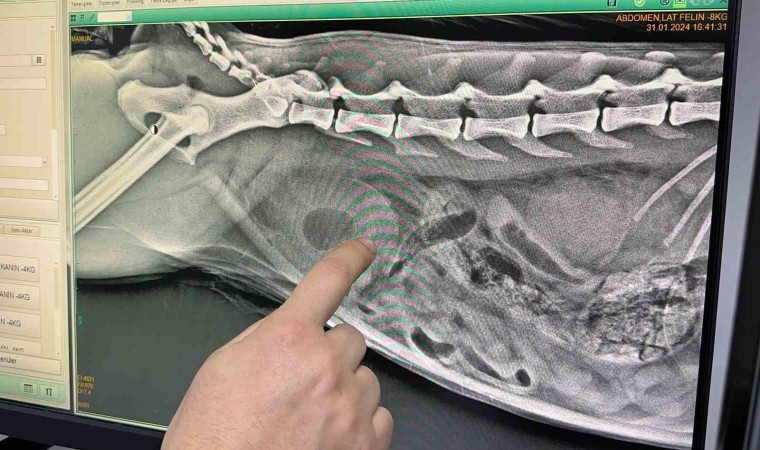

Zonguldak’ta sahibinin idrar yapamama şikayetiyle veterinere getirdiği kedinin idrar kesesinden çok sayıda kristal çıktı. Zorlu bir ameliyat süreci yaşadıklarını ifade eden Veteriner Hekim Gökmen Koç, kısırlaştırılan her 10 vakanın 4’ünde bu şikayetlerin görüldüğünü belirterek, "Böyle durumlarda ilk aklımıza gelen ve hasta sahibinden gelen ilk şikayet, ’Hocam acaba bu hayvan kabız mı oldu?’ oluyor. ’Kumuna gidiyor, saatlerce orada kalıyor’ şikayeti ile geliyorlar. Yaptığımız tetkiklerde idrar kesesinin dolu olduğunu gördük. Aldığımız röntgen ve ultrason görüntülerinde de bunu pekiştirdik. Hemen anestezi altında müdahale edildi. Ortalama yarım saat, 40 dakika o kristallerin atılmasını sağlamaya çalıştık. Zordu, güçtü. Meslek hayatımdaki en zor sondalamalardan biriydi. Burada idrar yolunu açmadan sondalamaya çalışmak kesinlikle çok daha kötü sonuçlanıyor. İdrar kesesini de yıkadıktan sonra amacımız şu anda idrar kesesinde biriken bütün tuzları eritmek."